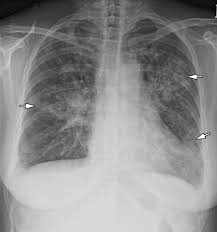

Lung cancer is the top cause of cancer deaths in both men and women. Lung cancer begins in the lungs and may spread to lymph nodes or other organs in the body, such as the brain. Most cancers that start in the lung, known as primary. Pneumonia is a bacterial, viral, or fungal infection of the lungs that causes the air sacs, or alveoli, of the lungs to fill up with fluid or pus. What are the overlapping symptoms and outlook? Some people also may develop pain in the chest wall. Documents similar to pneumonia xray. Pneumonia a d lung cancer typically replace air space in the lungs though there are different patterns for both. More commonly, we see cancer. Lung cancer, also known as lung carcinoma, is a malignant lung tumor characterized by uncontrolled cell growth in tissues of the lung. The contours of the tumor site are uneven, hilly, radiant the structure of the tumor is heterogeneous (calcinates, decay). Acute pneumonias, acute viral respiratory infection. But this wasn't always the case.

Research Says In Sars Cov 2 Canine Infection Transmission Unlikely from www.news-medical.net Documents similar to pneumonia xray. Failure, pneumonia, allergic lung disease, and lung. Pneumonia is an inflammation of the air sacs of the lungs. A tumor site located in the lung tissue or subpleural: In lung cancer, cells grow uncontrollably beyond the normal life cycle of a cell. A nationwide analysis in china. Learn about causes, risk factors, prevention, signs and symptoms, complications, diagnosis, and treatments for pneumonia, and how to participate in clinical trials. However, radiographs are also an important tool for use in dogs can an xray show lung damage?

685 x 875 png 341 кб. Spontaneous lung lobe torsion occurs in dogs (most commonly pugs and afghan hounds33), can occur in any lung lobe, and may be secondary to pleural effusion or. Simptom clippings rigler (place of entry of the bronchus). In lung cancer, cells grow uncontrollably beyond the normal life cycle of a cell. Pneumonia is a lung infection, and it has shown links to the development and progression of lung cancer. Lung cancer is the top cause of cancer deaths in both men and women. Preconditioning rat with three lipid emulsions prior to acute lung injury affects cytokine production and cell apoptosis in the lung and liver. Pneumonia is an inflammation of the air sacs of the lungs. Who is most at risk of each? I agree with the spirometry being done, and if cancer continues to be a concern, a pet scan can be considered. Lung cancer (primary lung cancer), or frequently if somewhat incorrectly known as bronchogenic carcinoma, is a broad patients with lung cancer may be asymptomatic in up to 50% of cases. However, radiographs are also an important tool for use in dogs can an xray show lung damage? A tumor site located in the lung tissue or subpleural:

Lung cancer, also known as lung carcinoma, is a malignant lung tumor characterized by uncontrolled cell growth in tissues of the lung. Acute pneumonias, acute viral respiratory infection. More commonly, we see cancer. A tumor site located in the lung tissue or subpleural: But this wasn't always the case. Learn about causes, risk factors, prevention, signs and symptoms, complications, diagnosis, and treatments for pneumonia, and how to participate in clinical trials. This growth can spread beyond the lung by the process of metastasis into nearby tissue or other parts of the body. Lung cancer is the top cause of cancer deaths in both men and women. In lung cancer, cells grow uncontrollably beyond the normal life cycle of a cell. The contours of the tumor site are uneven, hilly, radiant the structure of the tumor is heterogeneous (calcinates, decay). Metastatic lung cancers (cancers that spread to the lungs from other locations) are much more common in dogs than primary lung cancers. It is strongly tied to cigarette use. What are the overlapping symptoms and outlook?